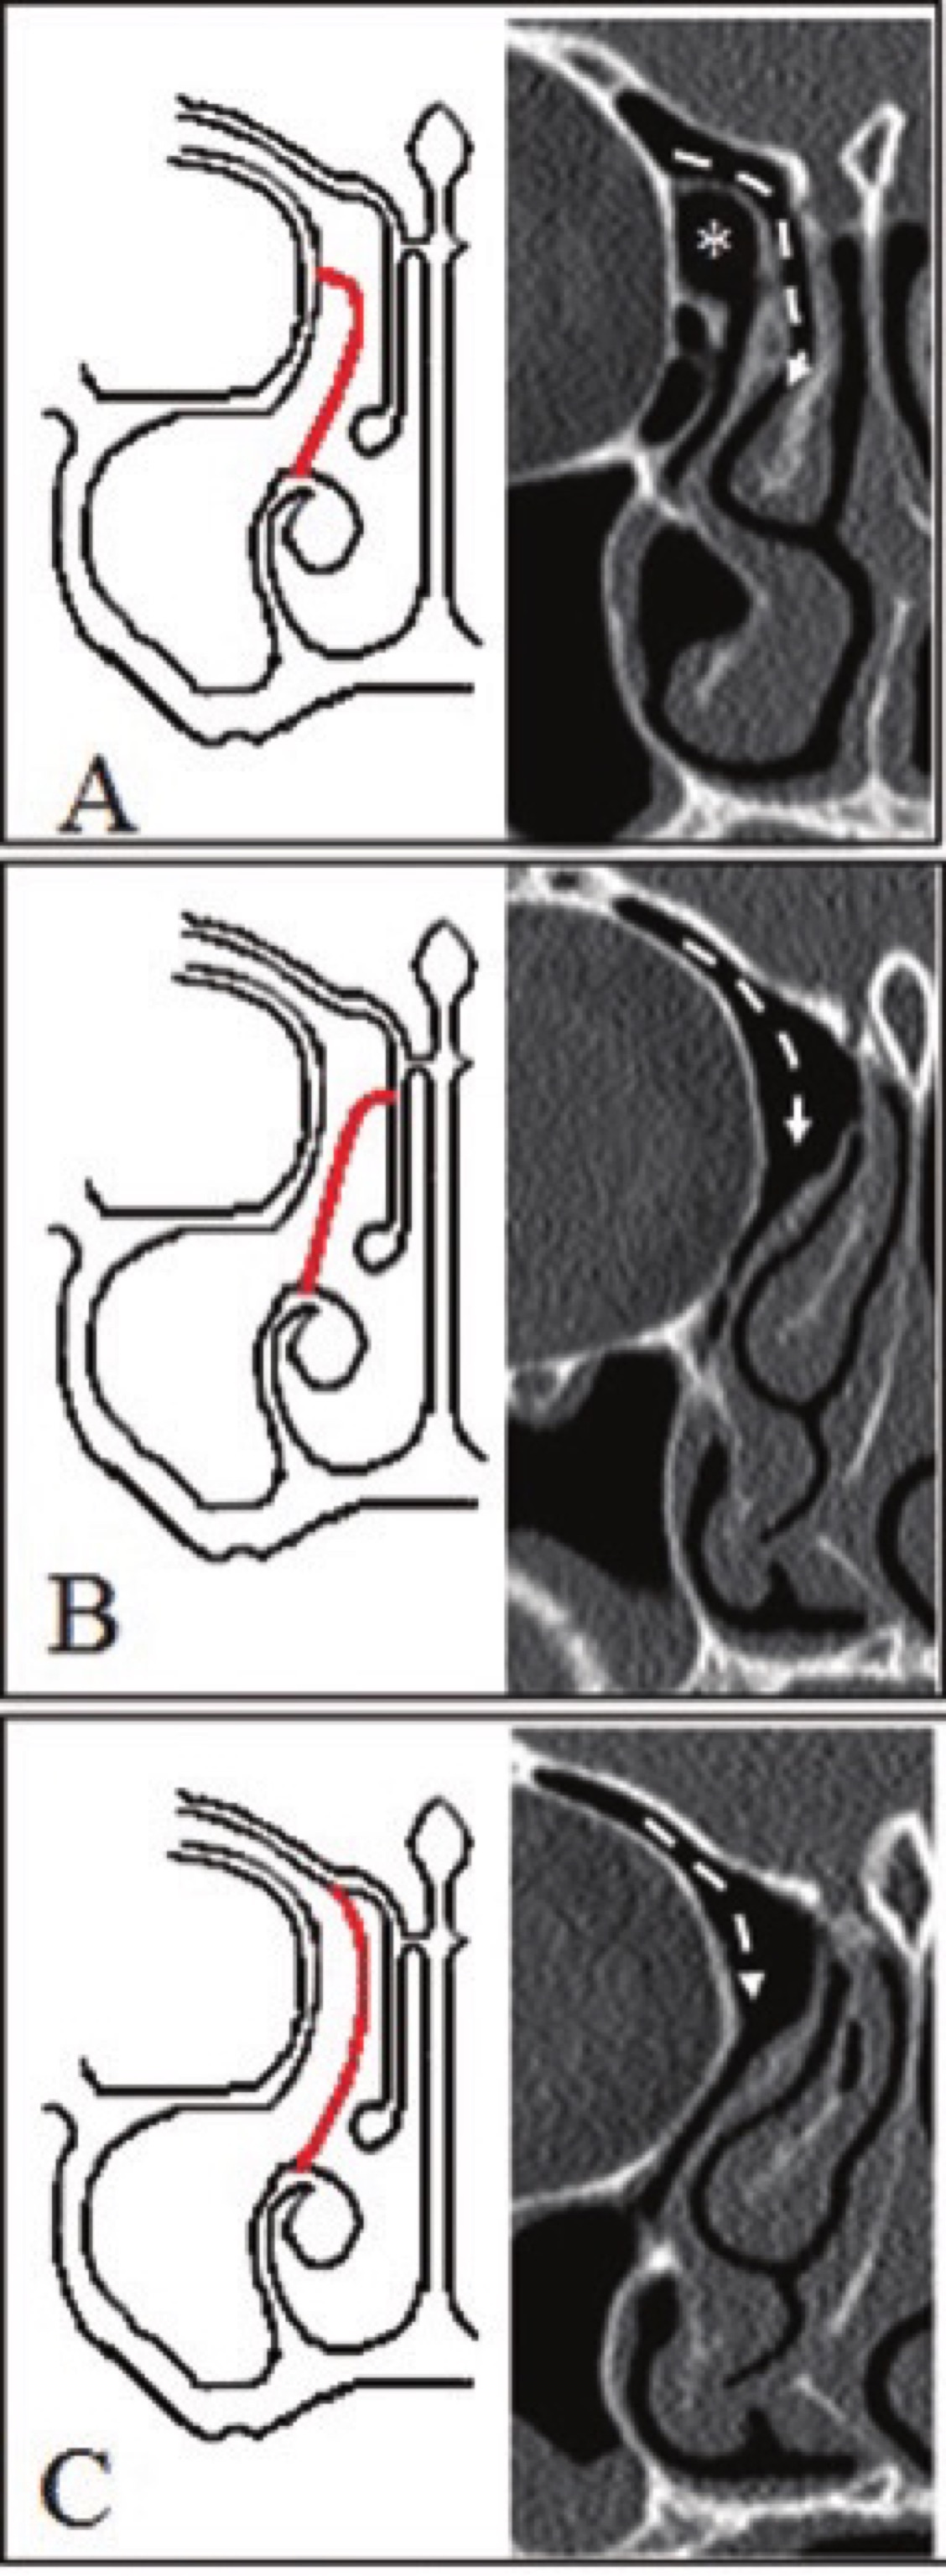

Foamy histiocytes (vacuoled macrophages) of Rhinoscleroma are called ___.

A

Mikulicz cells

How well did you know this?

1

Not at all

What is represented by the asterisk, according to the Kuhn classification?

Type IV Kuhn Cell

31

What is the Kuhn classification?

This describes 4 pneumatization patterns of the frontal sinus, and recess cells

32

What is Type 1 of the Kuhn classification of fronto-ethmoidal cells

A single cell superior to the agger nasi.

33

What is Type II of the Kuhn classification of fronto-ethmoidal cells

A tier of 2 or more cells above the agger nasi cell. (The asterisk indicates an Agger nasi cell)

34

What is Type III of the Kuhn classification of fronto-ethmoidal cells

A single cell extending from the Agger cell into the frontal sinus (the * indicates an Agger nasi cell)

35

What is Type IV of the Kuhn classification of fronto-ethmoidal cells

An isolated cell within the frontal sinus